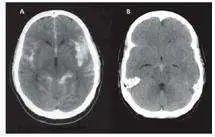

本題附上腦部電腦斷層攝影(CT)兩張影像(A、B):

- 影像 A:顯示基底腦池(basal cisterns)及側裂(sylvian fissures)呈現廣泛高密度(白色)訊號,這是蜘蛛網膜下腔積血的典型 CT 表現。正常腦脊髓液(cerebrospinal fluid, CSF)在 CT 上呈低密度(黑色),此處的高密度代表血液充填蜘蛛網膜下腔。

- 影像 B:右側半球可見局灶性高密度病灶,提示動脈瘤破裂部位附近可能合併局部腦內血腫(intraparenchymal hematoma)或動脈瘤瘤體內血塊,並可見環繞腦溝的血液。

整體影像符合典型的動脈瘤破裂引起的蜘蛛網膜下腔出血表現,搭配臨床上的雷霆頭痛(thunderclap headache)、癲癇發作及意識障礙,診斷明確。